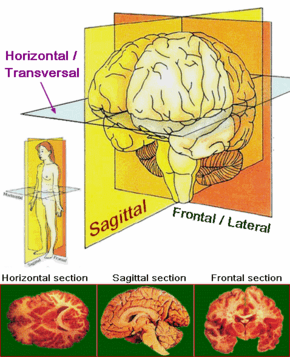

| Main anatomical planes and axes applied to the sections of the brain. | |